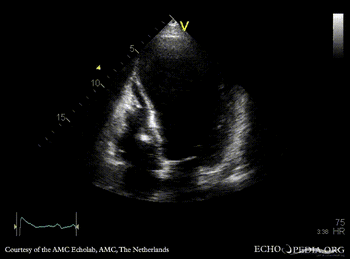

PSAX: dilated left ventricle, poor function